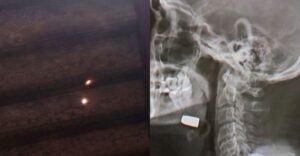

Na noite de sábado (13), a vítima procurou o Hospital Beneficente Dona Elmíria Silvério Barbosa devido à piora no quadro, segundo o site Noticidade. Após a realização de exames de imagem, foi constatado que ele estava com um projétil alojado na região do rosto, sendo necessária intervenção cirúrgica para a retirada.

Ainda de acordo com a vítima, ele dormia em sua casa quando sentiu forte ardência e dor, mas não chegou a ouvir estampidos de disparo. Apenas no período da tarde de sábado (13) percebeu um buraco no teto de sua residência, possivelmente causado pelo projétil que o atingiu.